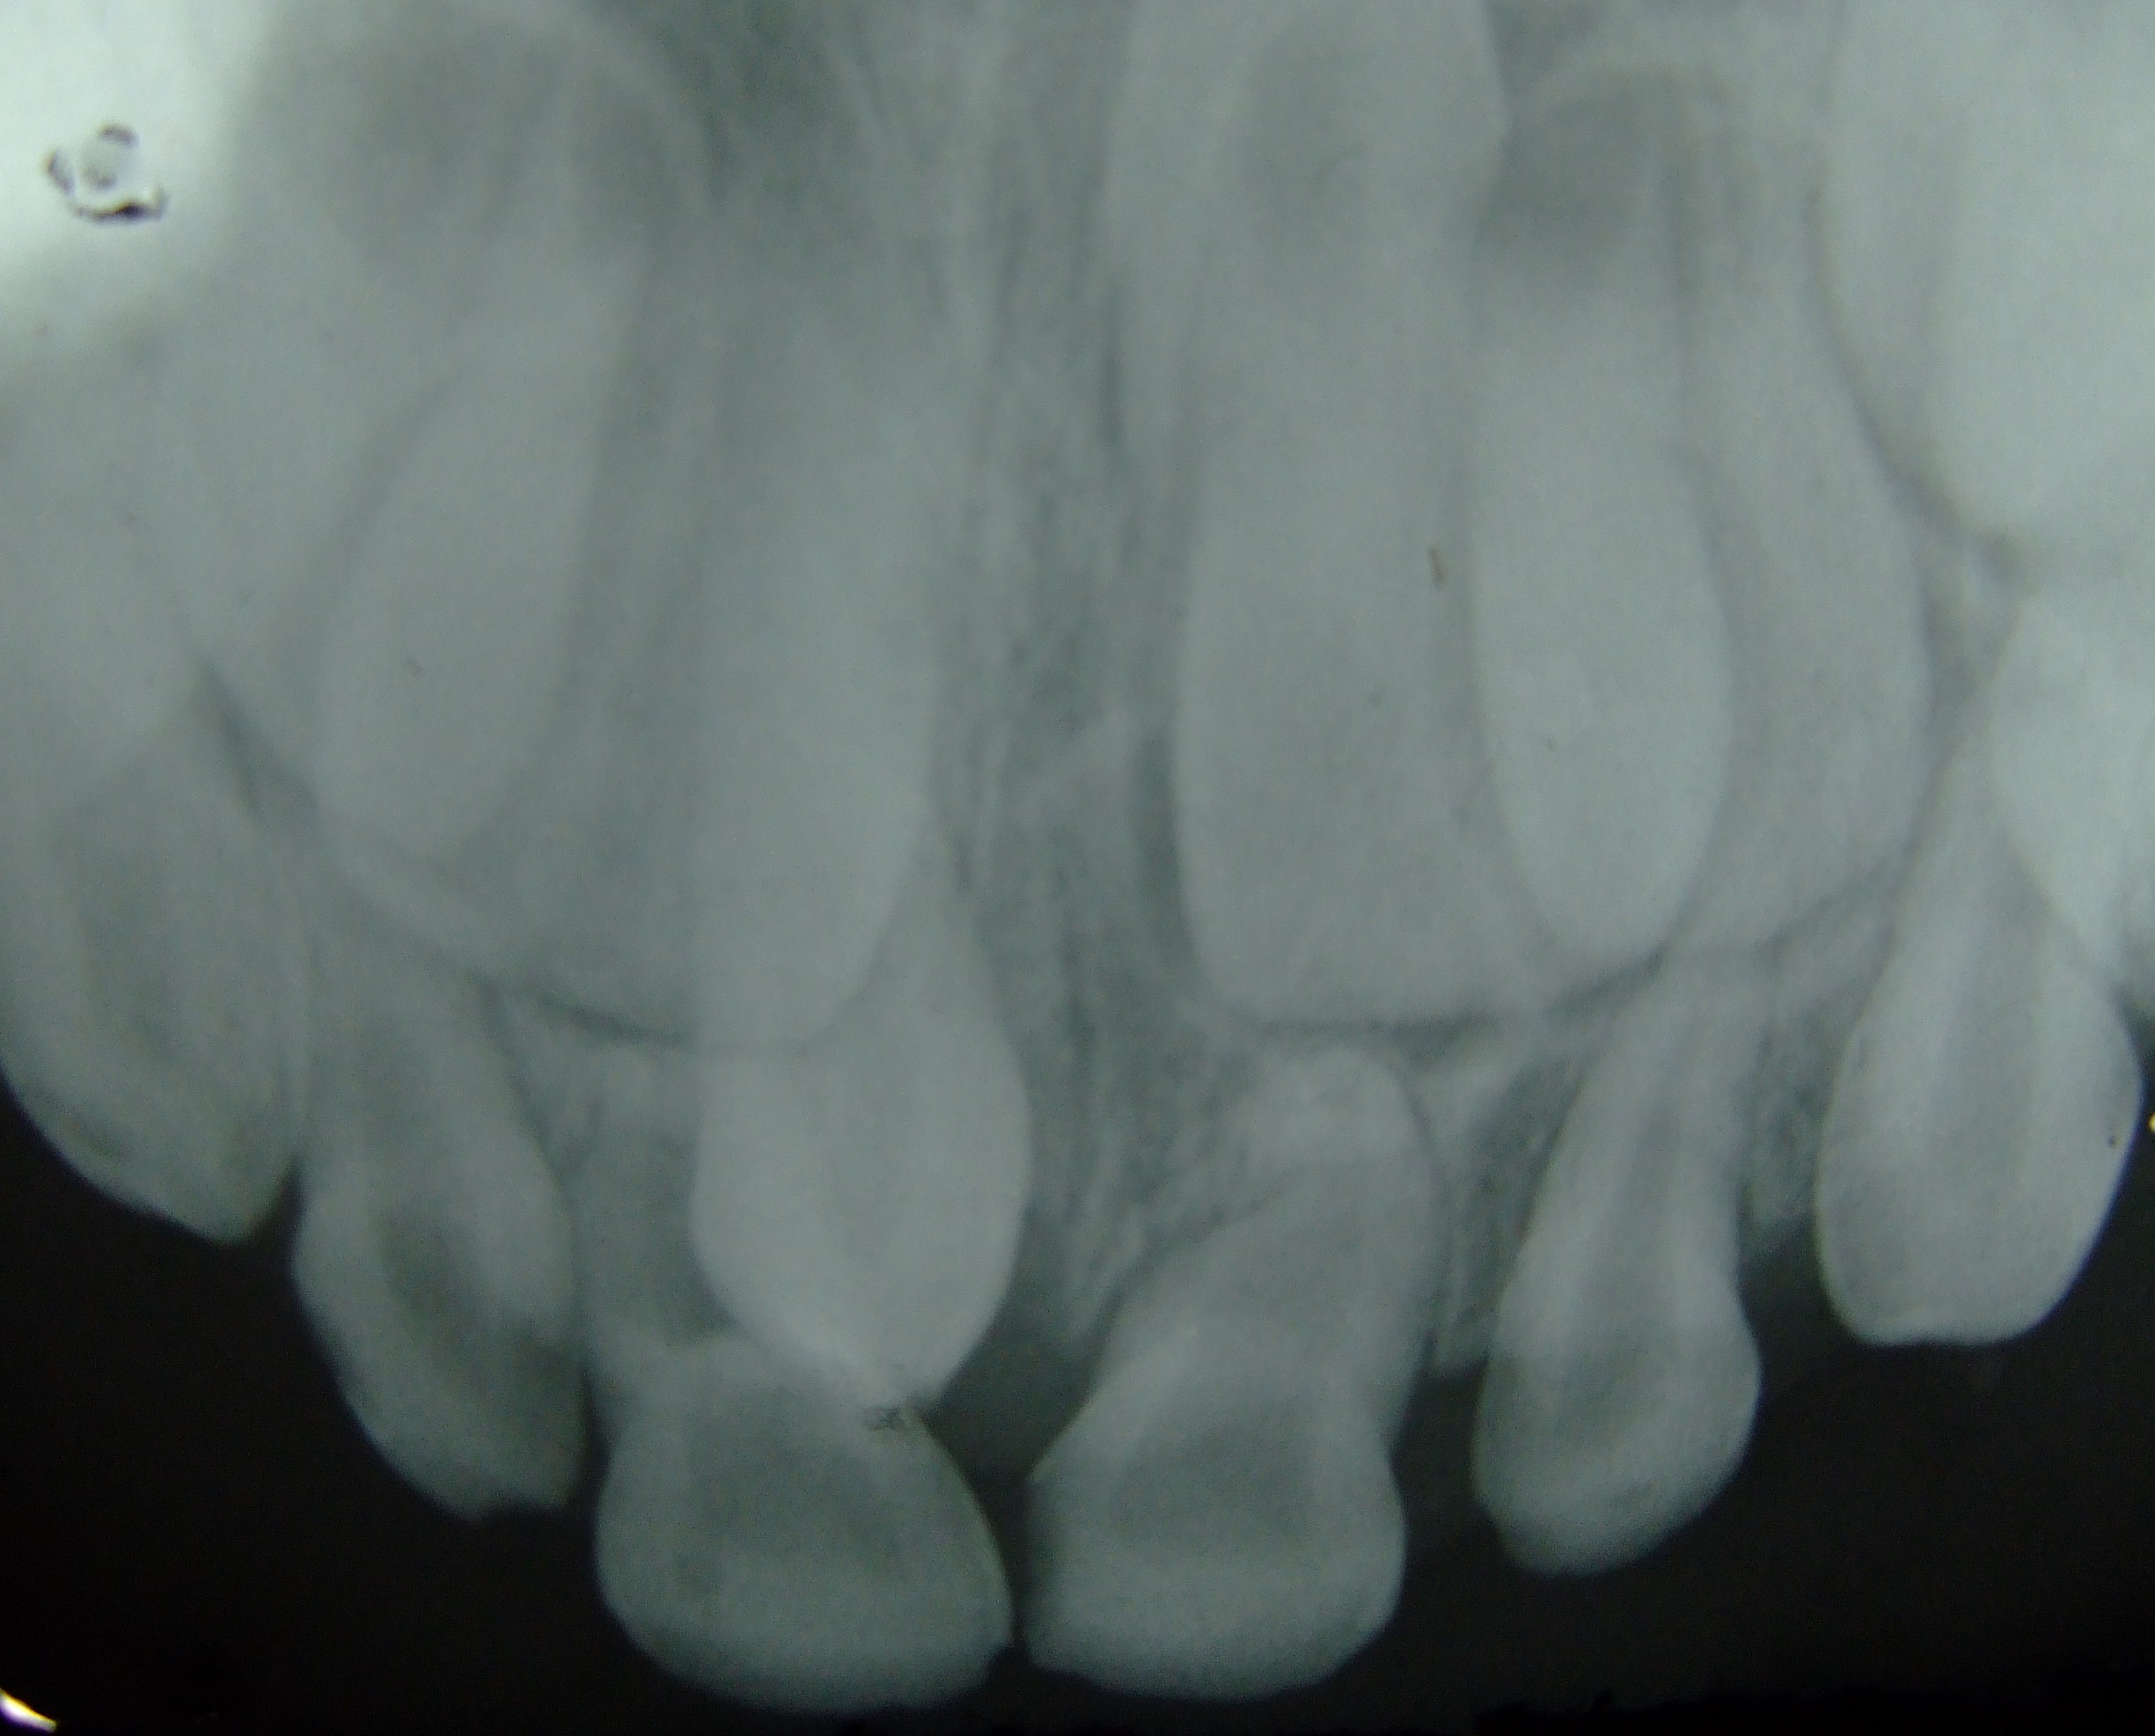

There are 32 slots, you can say, on your alveolus where teeth are expected (by your body) to be. Any teeth besides these 32 are considered supernumerary teeth. They can grow in the strangest of places; the roof of the mouth, above the teeth in rows like sharks, the palate, the bottom of the mouth, and yes, even the nostril. Usually they will stay close to where the other teeth are, and grow in some weird shape or form, often sharing space with other teeth.

That depends. Sometimes they are absolutely harmless, while other times they need to be removed for the safety of the patient. When there is more than one tooth in a place where there is supposed to be only one tooth, the problem of crowding occurs, causing the teeth to break, the alveolus to get over stretched, and the condition can lead to tooth decay, root canals and periodontitis as well. Sometimes the supernumerary teeth grow in places where it is difficult to clean or take care of. In these cases the tooth is likely to decay and to cause problems. But if you can clean it, it should not cause any problems a slong as the tooth is normally developed, which few supernumerary teeth are. Usually they have no roots, or very short roots, or they have very round cusps and are undifferentiated teeth. If this is the case, get rid of them, they are not doing anyíthing useful, and can potentially be infected at any point in time.